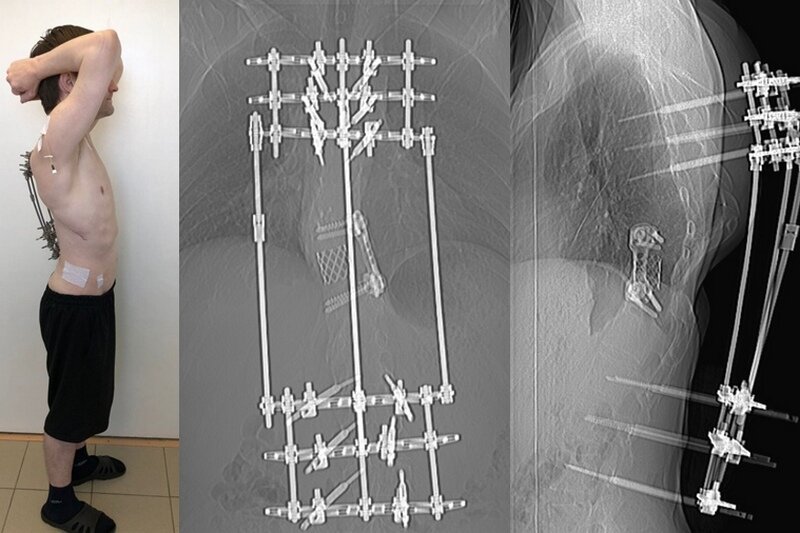

32-летний пациент из Татарстана впервые поступил в курганское учреждение в 2019 году в тяжелом состоянии с хондросаркомой позвоночника после нескольких операций, проведенных в других медцентрах. Установленный ему имплантат вызвал развитие хронической свищевой формы остеомиелита, мигрировав при этом из позвоночника в брюшную полость.

Врачи Центра Илизарова решили удалить металлоконструкцию и провести хирургическое лечение гнойной инфекции. Метод наружной фиксации позвоночника по Илизарову скомбинировали с ультрасовременным хирургическим подходом.

«Аналогов такой техники в настоящее время нет нигде в России», – заявил руководитель группы гнойной вертебрологии Клиники костно-суставной инфекции Центра Илизарова Максим Древаль.

Изобретение выдающегося ученого Гавриила Абрамовича Илизарова помогло устранить деформацию позвоночника и расклинить позвонки для проведения основной операции для сращения передней колонны позвоночника, сообщили в пресс-службе медучреждения.

Врачи установили раздвижной имплантат. Спустя два месяца систему внешней фиксации демонтировали. Пациент поехал домой на своих ногах в хорошем самочувствии.

Фото предоставлено НМИЦ ТО им. акад. Г.А. Илизарова Минздрава РФ